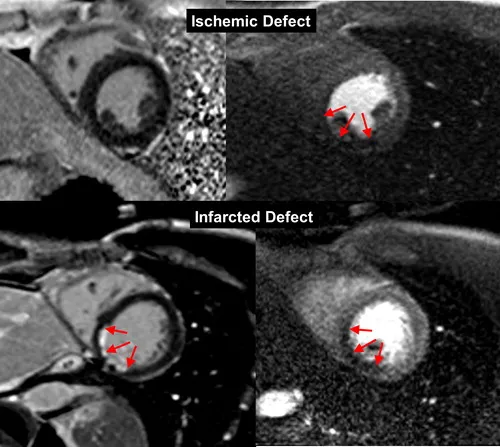

BJR publishes special feature on imaging patients with stable chest pain. BJR, the international research journal of the British Institute of Radiology, has published a collection of articles on the theme of imaging patients with stable chest pain, guest-edited by leading experts Professor Matthijs Oudkerk & Professor Edwin van Beek. Millions of people around the world suffer from chest pain. Diagnosing the cause of chest pain & identifying the level of risk are integral to the prevention of serious coronary events & poor patient outcomes. Imaging is central to these efforts & provides vital information to primary care physicians, cardiologists & the variety of doctors who manage patients with stable chest pain. Following the publication of the SCOT-HEART trial in 2015 (a study to see if coronary artery calcium score & computed tomography coronary angiogram alters the proportion of patients diagnosed with angina due to coronary heart disease), a new era of non-invasive coronary imaging has opened up. This BJR special feature covers many of the important topics & questions facing the scientists & clinicians working in the field & presents a collection of insightful Review articles & Commentaries from leading international experts. Professor Edwin van Beek said “This special feature is essential reading for any medical professionals interested in stable chest pain. The articles cover vital topics such as vulnerable plaque, cost-effectiveness for imaging stable ischemic disease, the potential for functional coronary & cardiac CT imaging, the role of machine learning, the role of MRI for the assessment of chest pain & the role of imaging in the evaluation of heart valve disease”. Professor Matthijs Oudkerk explains “This special feature marks the moment of publication of the first hard evidence that non-invasive coronary CT imaging in patients with chest pain saves lives compared to current medical practice & at the same time is a lot less harmful for the patient, costs less & is more effective. This special feature is not to be missed!”. You can access the special feature, here. Image Figure 1 from \"MRI perfusion in patients with stable chest-pain\" Images Figure 1 from "MRI perfusion in patients with stable chest-pain" Figure 1. The top row is an example of an ischemic perfusion defect, where the stress perfusion image shows a clear hypoperfused area (red arrows), whereas the LGE image shows no defect. The bottom row shows an infarct-related perfusion defect, where on both, stress perfusion (slightly hypoenhanced tissue, red arrows) and LGE image (strongly hyperenhanced tissue) a defect is shown (red arrows). This example of an infarct patient also demonstrates the superiority of LGE to delineate scar in comparison to the perfusion approach. In scar, the extracellular Gd-chelate contrast medium distributes in a large extracellular (fibrotic) compartment during first-pass, which increases the signal in the fibrotic tissue explaining its reduced sensitivity to detect hypoperfusion in scar. This reduced sensitivity to detect hypoperfusion is not observed in viable myocardium (with small extracellular compartment). LGE, late gadolinium enhancement. Image Figure 4 from \"Non-invasive imaging of high-risk coronary plaque: the role of computed tomography & positron emission tomography\" Figure 4 from "Non-invasive imaging of high-risk coronary plaque: the role of computed tomography & positron emission tomography" Figure 4. 18F-GP1 arterial uptake in right popliteal artery. 18F-GP1 PET-CT images of a patient who had recently undergone right common femoral artery endarterectomy & right popliteal artery angioplasty. Anterior maximum intensity projection & axial images taken 120 min after 18F-GP1 injection show focal increased uptake in the right popliteal artery (a, b); arrows), which corresponds to a thrombotic lesion after angioplasty (c). Additional 18F-GP1 uptake is seen in the dissected right distal external iliac artery (d, e); dotted arrows) & right common femoral artery (a, f); arrow heads) where endarterectomy was performed 3 days prior to the PET-CT (g, arrow head). Images courtesy of Chae et al.40 PET, positron emission tomography. Image Figure 5 from \"Vulnerable plaque imaging using 18F-sodium fluoride positron emission tomography\". Figure 5 from "Vulnerable plaque imaging using 18F-sodium fluoride positron emission tomography" Figure 5. Examples of coronary plaques with significant uptake on 3 h PET & low tracer activity of 1 h post injection imaging. Short axis images of proximal left anterior descending, proximal circumflex (A) & distal right coronary artery (B) plaques (arrows) which had a TBR <1.0 on 1 h PET (left column) & showed uptake exceeding the 1.25 TBR threshold at 3 h. This research was originally published in JNM. Kwiecinski J, Berman DS, Lee SE, Dey D, Cadet S, Lassen ML, Germano G, Jansen MA, Dweck MR, Newby DE, Chang HJ, Yun M, Slomka PJ. Three-Hour Delayed Imaging Improves Assessment of Coronary 18F-Sodium Fluoride PET. J Nucl Med. 2019 Apr;6025 :530–535. doi: 10.2967/jnumed.118.217885. PET, positron emission tomography; SUV, standardized uptake value; TBR, target to background ratio. Related links British Institute of Radiology British Journal of Radiology British Journal of Radiology special feature Professor Edwin van Beek Professor David Newby Professor Marc Dweck SCOT-HEART What is a CT scan? What is a PET scan? What is a MR scan? What is a PET-CT scan? "MRI perfusion in patients with stable chest-pain" "Non-invasive imaging of high-risk coronary plaque: the role of computed tomography & positron emission tomography" "Vulnerable plaque imaging using 18F-sodium fluoride positron emission tomography" Social media tags & titles BJR publishes special feature on imaging patients with stable chest pain. @BIR_News @BJR_Radiology @SINAPSECENTRE @MarcDweck #ChestPain Publication date 16 Sep, 2020